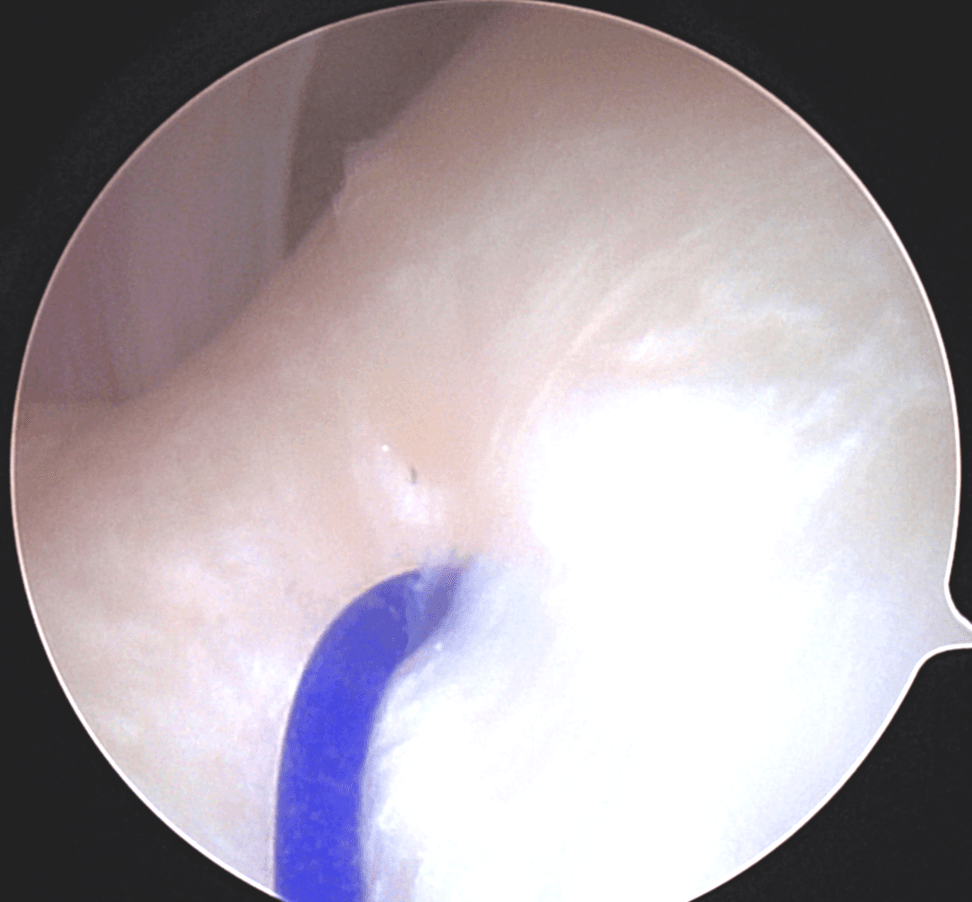

Certains DTM par contre nécessiteront une approche chirurgicale en raison de leur nature ou de l’impact significatif qu’ils ont sur la fonction. En règle générale, le chirurgien tend à choisir l’approche minimalement invasive qui est la plus appropriée dans les circonstances. Cela peut impliquer une simple infiltration articulaire, une chirurgie sous caméra (arthroscopie; approche qui permet d’avoir accès et manipuler le contenu articulaire sans avoir à ouvrir) ou dans certains cas une chirurgie ouverte (arthrotomie). Les Drs Poirier et Badri détiennent notamment des expertises dans ces champs de pratiques de par leur expérience et leur surspécialisation.

Chirurgie sous arthroscopie